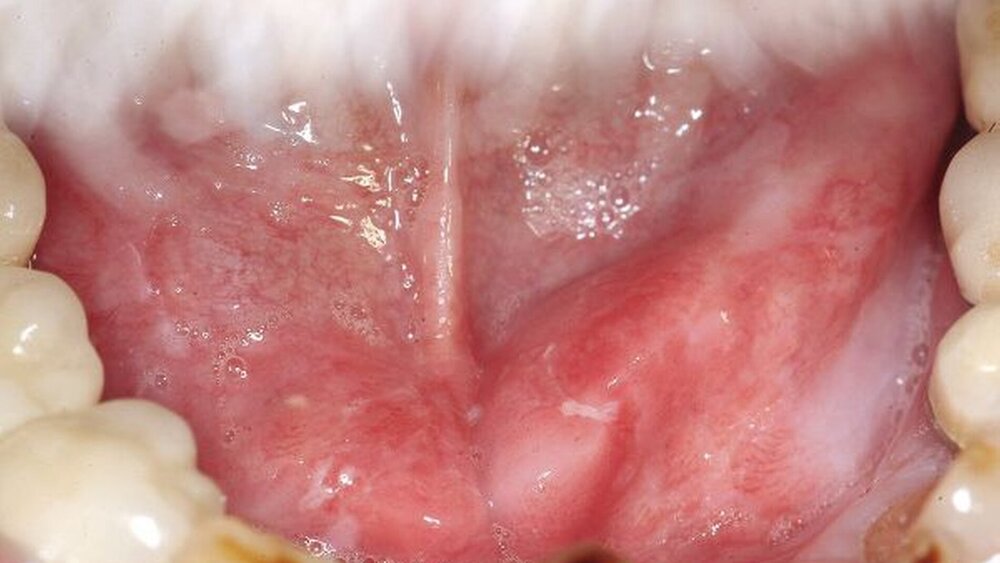

Mundkrebspatienten haben eine veränderte Mundflora

Die Wissenschaftler analysierten die Zusammensetzung der Mundflora von 40 Probanden mit einem Plattenepithelkarzinom im Vergleich zu gesunden Patienten. Zur Untersuchung der einzelnen Bakterienstämme verwendeten sie ein hochmodernes Verfahren des Next Generation Sequencing (NGS), das mithilfe des Illumina-MiSeq-Systems arbeitet. Damit konnten sie mehr als fünf Millionen bakteriellen Genomen bearbeiten. Die Forscher detektierten insgesamt elf Bakterienstämme, 130 Bakteriengattungen und nahezu 390 verschiedene Bakterienspezies in ihren gewonnenen Proben.